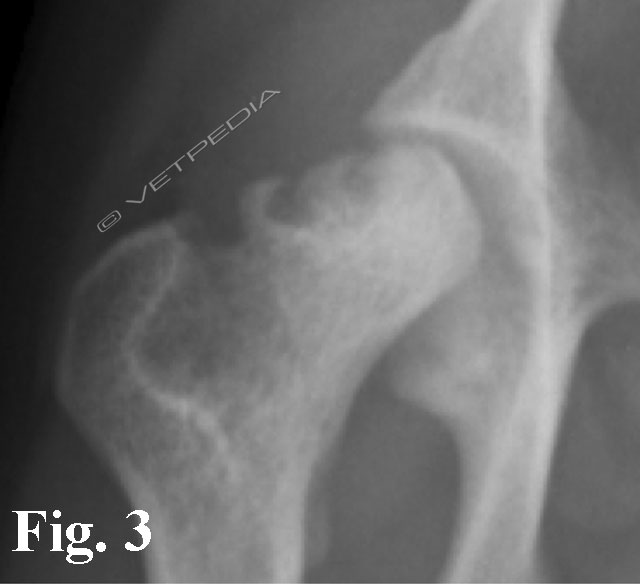

{{/_source.additionalInfo}}La necrosi asettica della testa del femore è anche denominata malattia di Legg Calvè Perthes e necrosi avascolare della testa del femore. Si tratta di un'affezione ortopedica coinvolgente l’articolazione coxofemorale di cani di razza toy o di piccola taglia durante il periodo dell’accrescimento, ad interessamento più frequentemente monola